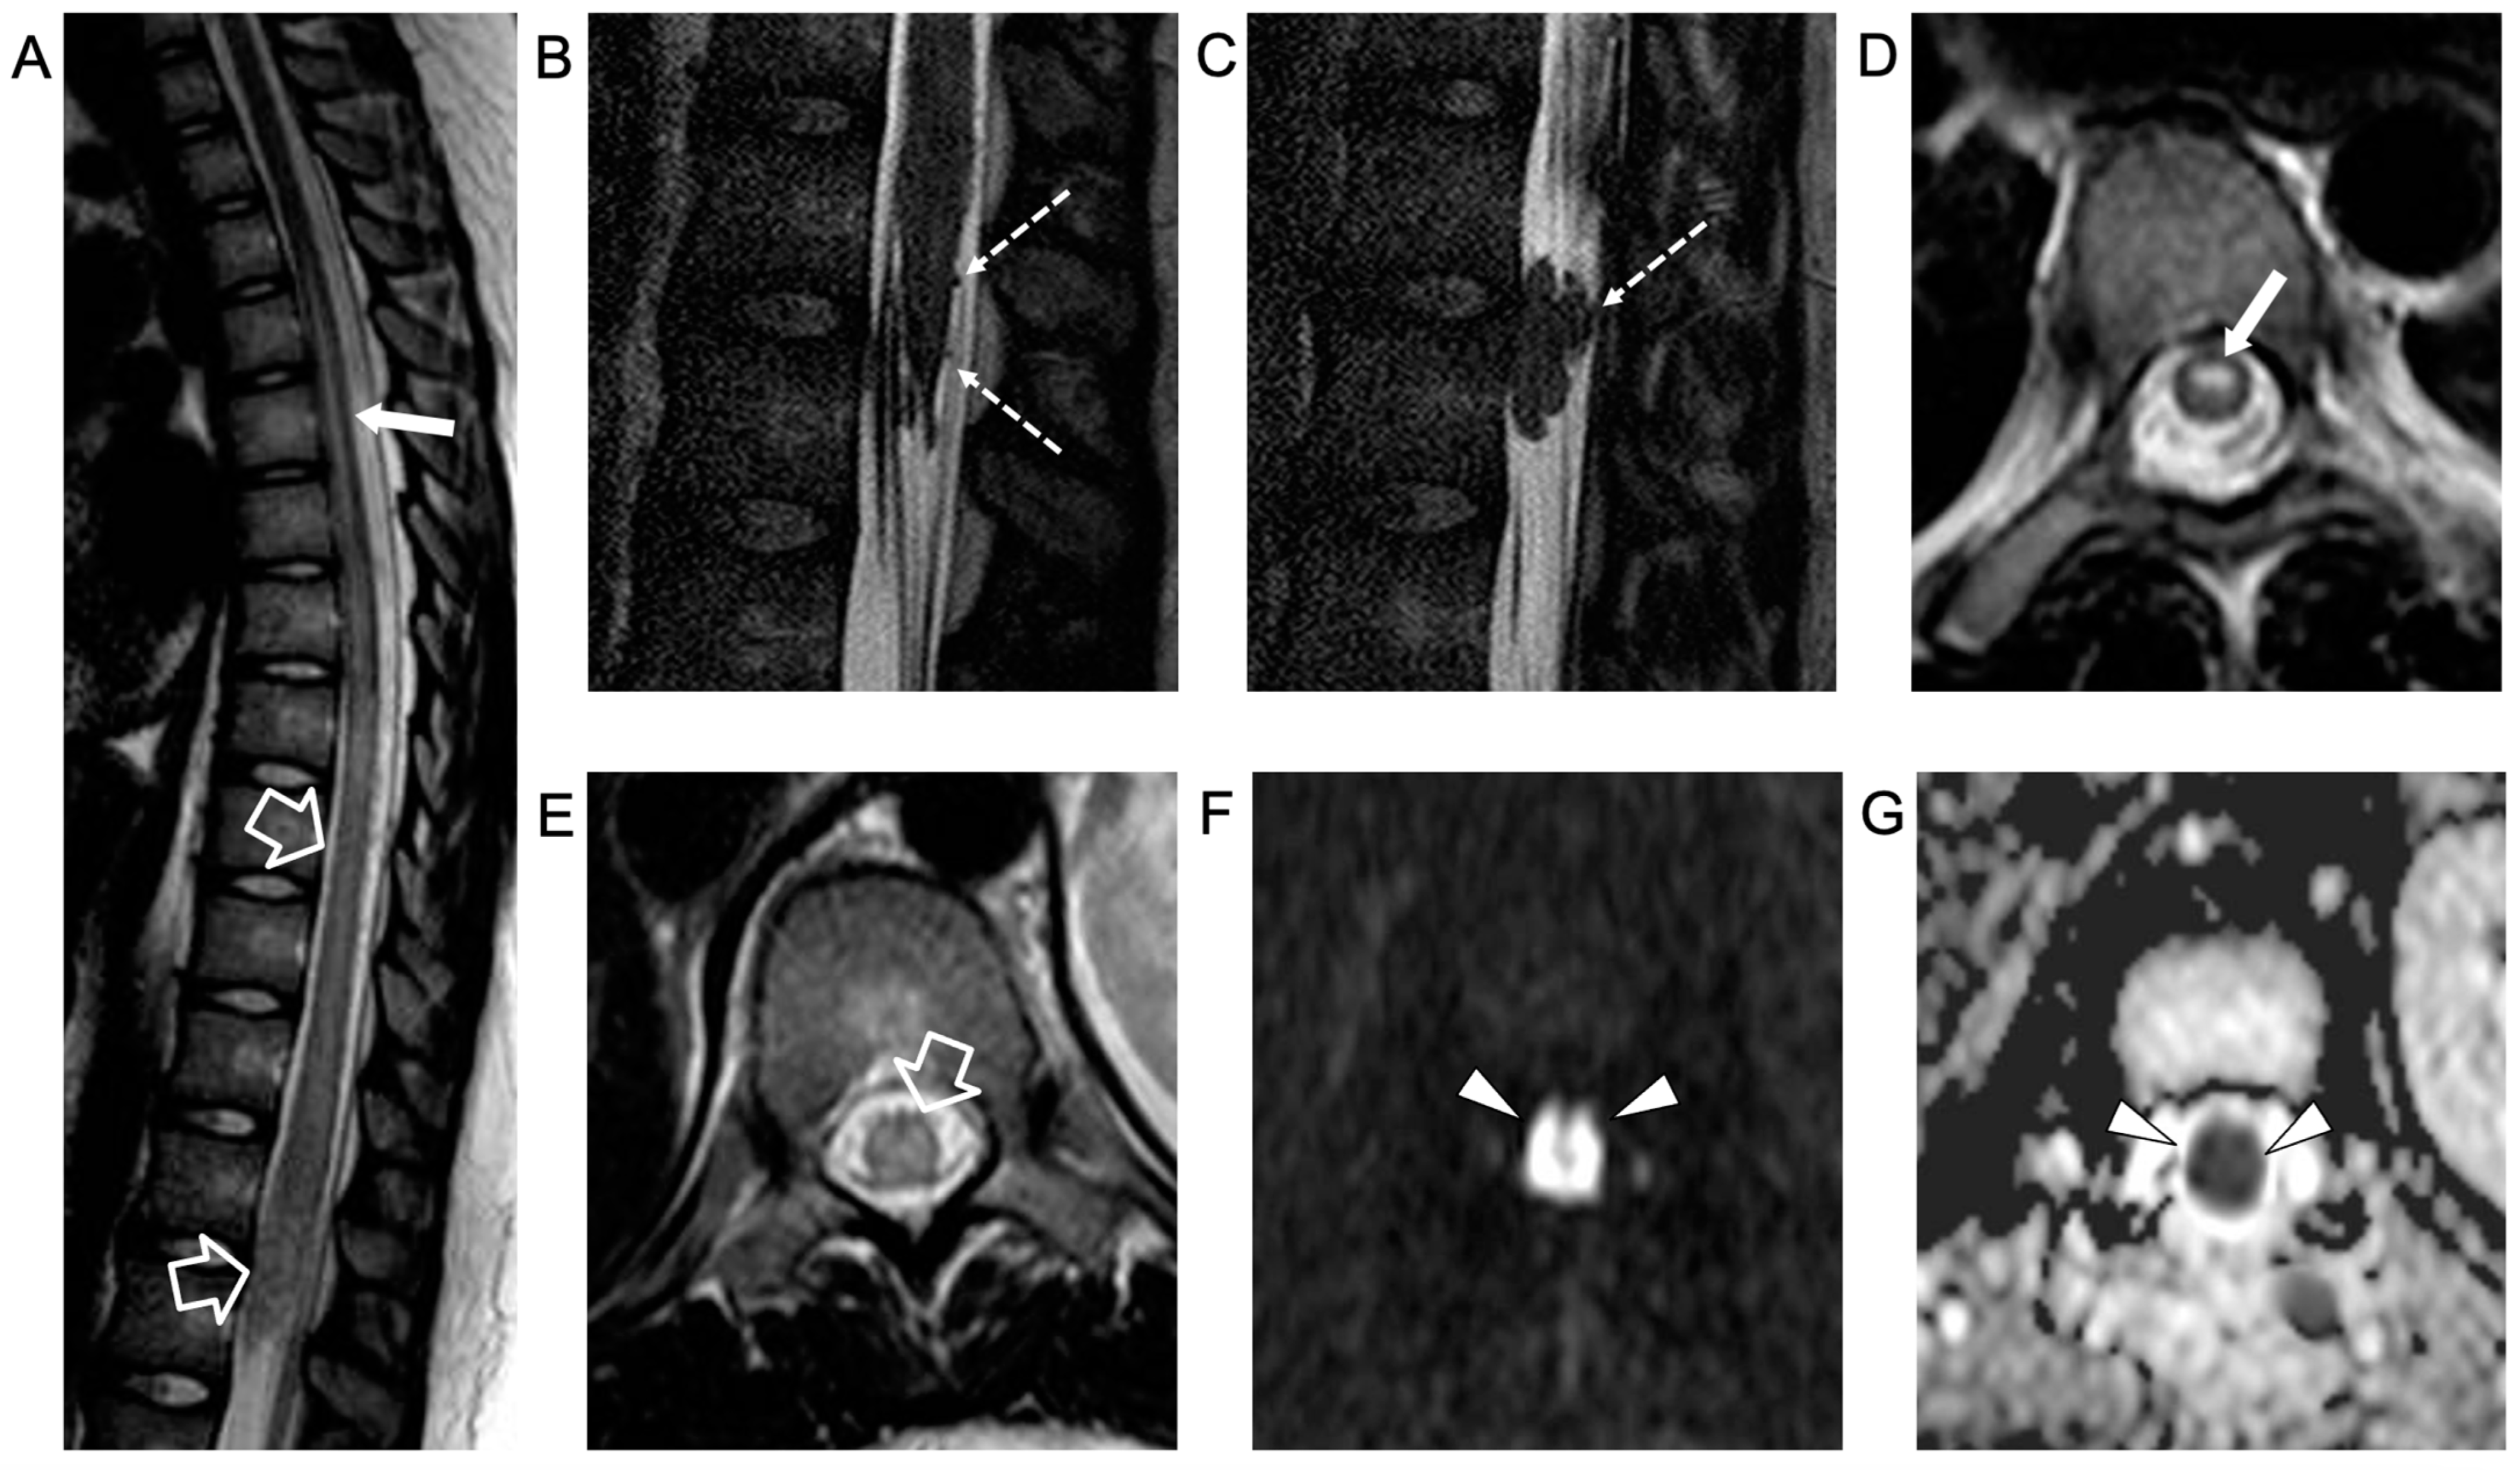

2. Case Report